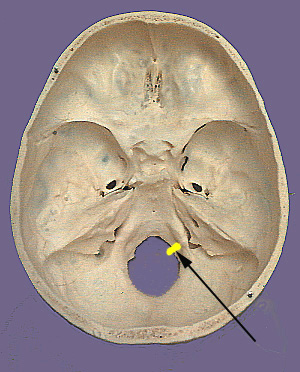

The hypoglossal nerve as the name indicates can be found below the tongue.  It is a somatomotor nerve that innervates all the intrinsic and all but one of the extrinsic muscles of the tongue.  The neuronal cell bodies that originate the hypoglossal nerve are found in the dorsal medulla of the brain stem in the hypoglossal nucleus.  This nucleus gives rise to axons that exit as rootlets that emerge in the ventrolateral sulcus of the medulla between the olive and pyramid.  The rootlets come together to form the hypoglossal nerve and exit the cranium via the hypoglossal canal.  The nerve passes laterally and inferiorly between the internal carotid artery and internal jugular vein.  The twelfth cranial nerve travels lateral to the bifurcation of the common carotid and loops anteriorly above the greater horn of the hyoid bone to run on the lateral surface of the hyoglossus muscle.  It then travels above the edge of the mylohyoid muscle.  The hypoglossal nerve then separates into branches that supply the intrinsic muscles and three of the four extrinsic muscles of the tongue.